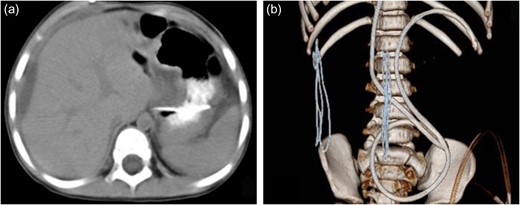

A female child, at the age of 2 years, was admitted to our hospital because she was not able to walk alone. This child patient had undergone ventriculo–peritoneal (VP) shunt procedure for hydrocephalus confirmed by magnetic resonance imaging (MRI). On the 50th day after the surgery, she mainly complained of intermittent fever and mild abdominal pain for 12 days. Physical examination showed no obvious abnormality. Blood routine examination showed white blood cell count was 8.31 × 109/l, with neutrophils 60.7%, lymphocytes 30.8%. C-reactive protein was 81 mg/l. Abdominal ultrasonography indicated ascites. Abdominal enhanced computed tomography (CT) scan showed that water-like hypointense mass in sub-capsular of liver, which was homogeneous and well-defined, the max cross-sectional area was ~6.04 × 3.85 cm, multiple catheter images were seen in abdominal cavity, also showed that there was no enhanced images in the mass (Fig. 1). Accordingly, it was necessary to perform exploratory operation. Operation found that a little of clear fluid was accumulated in abdominal cavity and the distal end of catheter was located at the sub-capsular of diaphragmatic surface of right liver. The distal end was pulled out slowly and sub-capsular effusion overflowed. The VP shunt catheter was neither disconnected nor fractured, and was replaced subsequently in abdominal cavity. Postoperative CT scan showed that a small part of effusion remained in the liver contour and the distal catheter in the left abdominal cavity (Fig. 2). The child was discharged uneventfully in 1 week postoperative.

The enhanced CT before operation. (a) Axial CT showed water-like hypointense mass and catheter image in the liver contour. (b) Sagittal CT revealed catheter image under liver capsule and the homogeneous and well-defined mass in the liver contour. (c) Three-dimensional image of catheter in abdominal cavity. (d) The mass in the liver contour.